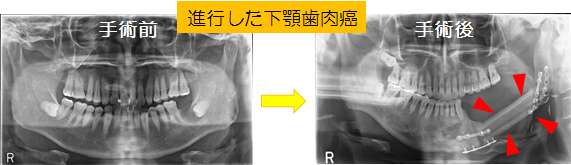

口腔がんの治療法には 手術・放射線療法・化学療法(抗癌剤)の3つがありますが、最も有力な治療法は 手術 です。

しかし、進行がんでは舌や顎を大きく切除し、その後再建が必要となり、

- 容貌が変わる

- 感覚が麻痺する

- 味覚が失われる

- 噛めない

- 飲み込めない

などの後遺症が残ることがあります。

口腔癌は助かったとしても発見が遅れれば、舌・顎・頬を大きく切除する大変「悲惨ながん」です…。